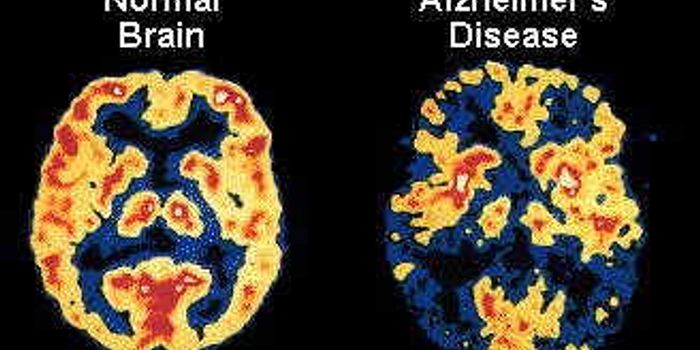

JUL 16, 2019Health & MedicineCurrently, to gauge the risk of Alzheimer’s disease, patients must undergo brain scans, spinal fluid tests, or men ...

OCT 29, 2021InfographicsAlzheimer's is the most common form of dementia, an umbrella term for different kinds of cognitive decline inlcuding ...

NOV 13, 2017InfographicsIn 1983, President Ronald Reagan designated November as National Alzheimer’s Disease Awareness Month. As it turns ...